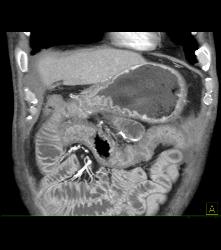

Antral Carcinoma